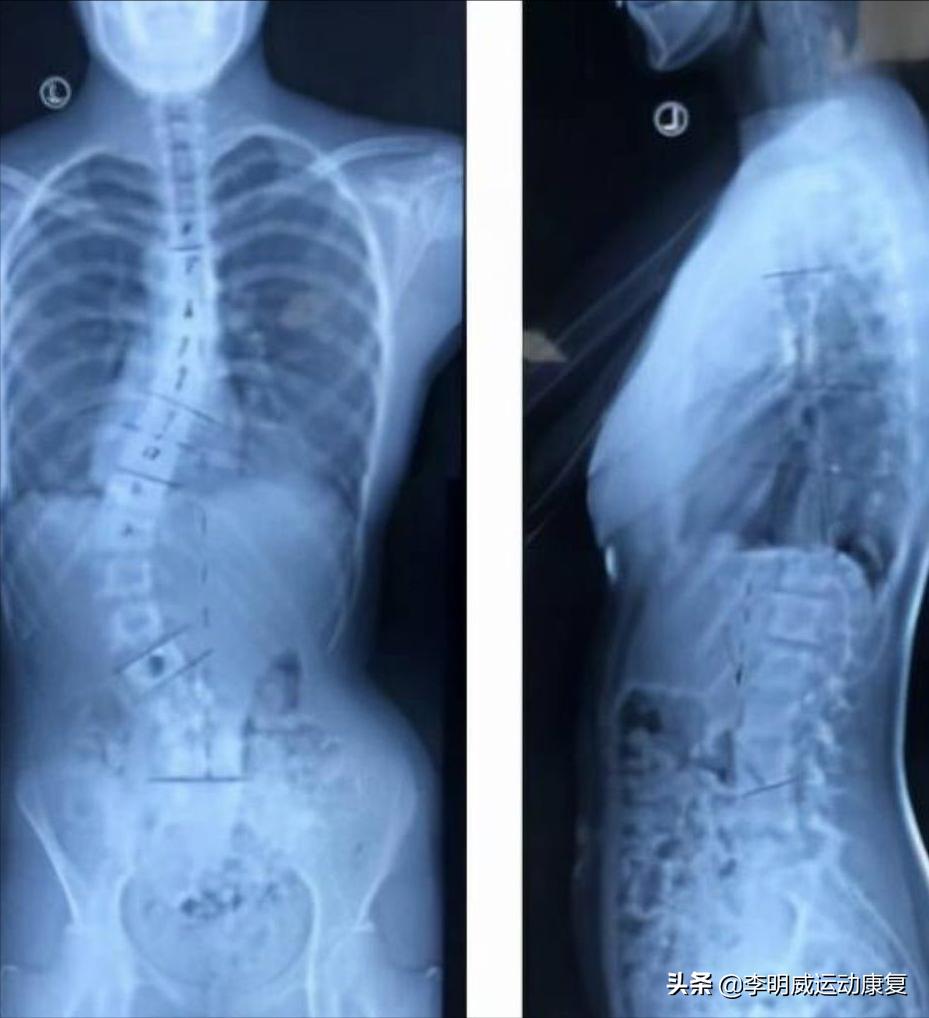

我给大家看一个脊柱侧弯的X光片,你可能会更加了解。

下面这个是很严重的,我看着都很心痛。

其实这些都是从轻微发展而来的,到比较严重都要经过几年的时间,这个时期一定要及时发现和纠正,要不然等到成年了就会非常难。